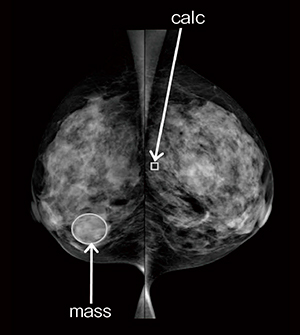

さらに,読影モニタに表示されたCADイメージには,微細石灰化の集団を示唆する領域に長方形のマークが,腫瘤や構築の乱れに該当する可能性のある領域には楕円のマークが表示されます(図1)。このようなRCへのマーカーの表示は,放射線科医の読影をサポートし,読影の信頼性を改善します。

図1 CADによるRCの表示